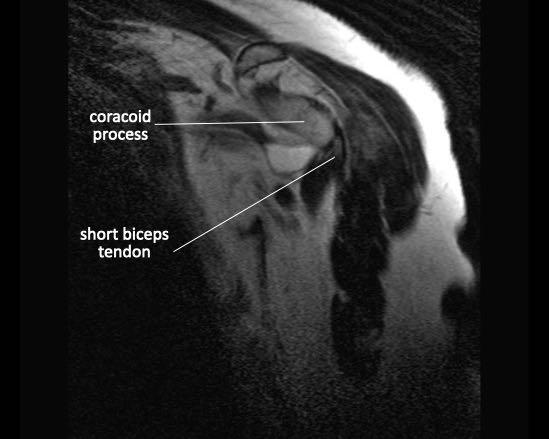

Đầu dài gân cơ nhị đầu

Đầu dài gân cơ nhị đầu có liên quan về mặt giải phẫu và chức năng với chóp xoay. Gân xuất phát từ củ trên ổ chảo và đoạn gần của nó nằm trong khớp. Gân thoát ra khỏi khớp ổ chảo – cánh tay và đi qua khoảng gian cơ xoay giữa gân cơ dưới vai và gân cơ trên gai vào rãnh gian củ của đầu trên xương cánh tay.

Gân cơ nhị đầu

Đầu dài của gân cơ nhị đầu bám vào củ trên ổ chảo. Sau đó, gân chạy qua khớp ổ chảo – cánh tay và khoảng gian cơ chóp để thoát ra phía trước khớp trong rãnh gian củ.

Gân cơ nhị đầu có vai trò ngăn chặn sự di chuyển lên trên của chỏm xương cánh tay.